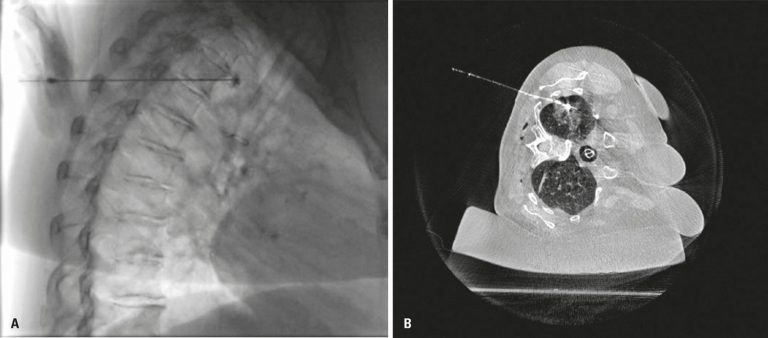

A total of 20 patients were included and submitted to descriptive analysis. All patients were marked in a hybrid room, at the same surgical-anesthetic time. Most often used markers were guidewire, Lipiodol® and microcoils. Despite one case of coil displacement, two cases of pneumothorax, and one case of hypotension after marking, all lesions were identified and resected accordingly from all patients.